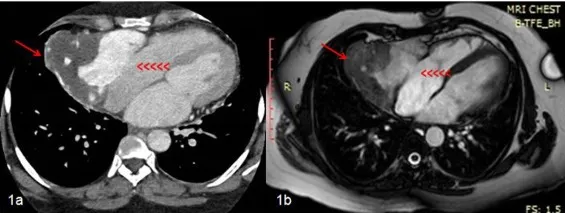

- Diagnosis: Echo, CT, MRI. Biopsy for confirmation.

⭐ Angiosarcoma, the most common primary malignant cardiac tumor, often arises in the right atrium and may cause hemorrhagic pericardial effusion.

Metastatic Cardiac Tumors - Secondary Spread

- Significantly more common than primary cardiac tumors, occurring 20-40 times more frequently.

- Pericardium is the most common site, followed by myocardium, then endocardium.